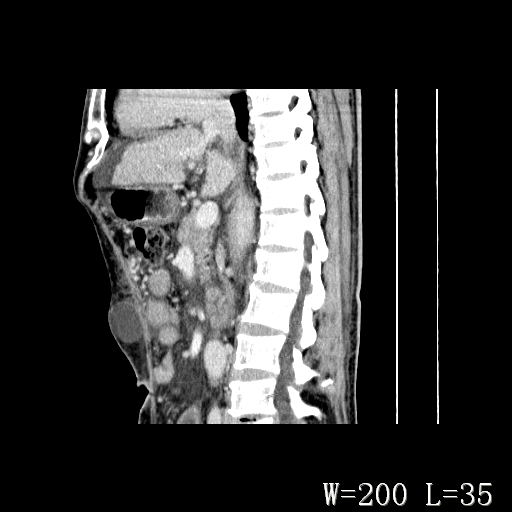

男,52岁,门脉高压断流术后1年,发现腹部肿物2月。

1)前腹壁中线区(脐上方)囊性占位性病变,考虑淋巴囊肿。2)腹水。